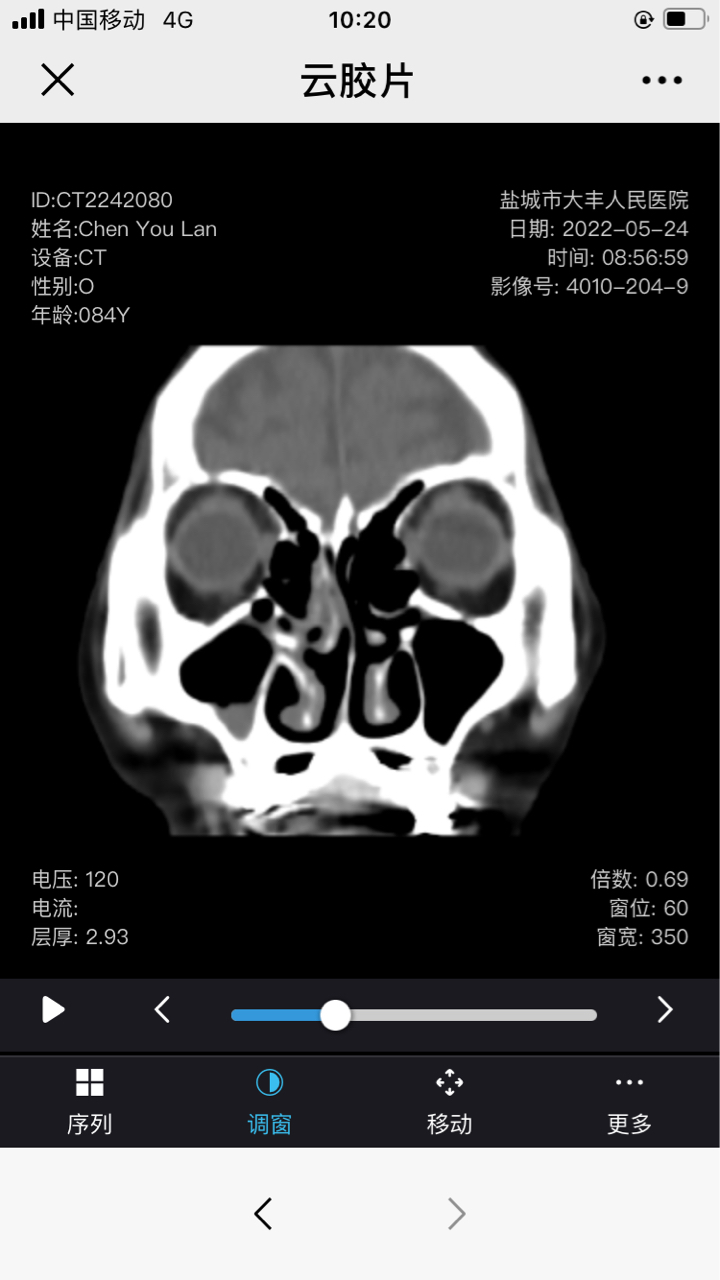

奶奶近两月鼻腔一直出血,有时带脓,初诊为鼻炎鼻窦炎,药物治疗效果不好。Ct也没说什么。活检说怀疑淋巴癌。急!

这是Ct报告